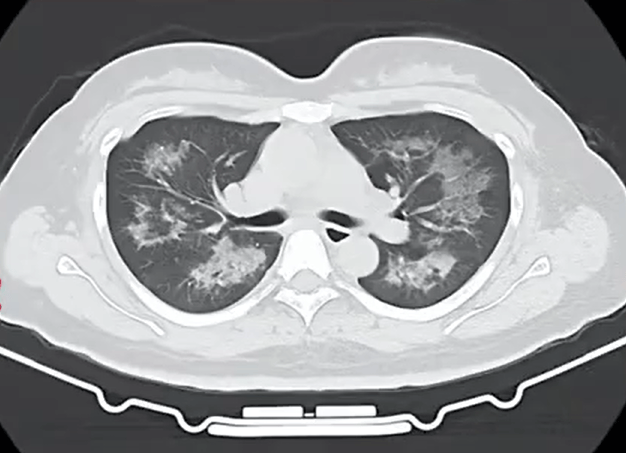

胸部CT进一步显示,她的双肺出现多发斑片状模糊影,被诊断为间质性肺炎。医生判断,病因很可能与她近期长期接触的某类物质相关。经过医生反复细致地询问病史,小江才说出自己存在长期、频繁使用定妆喷雾的情况。